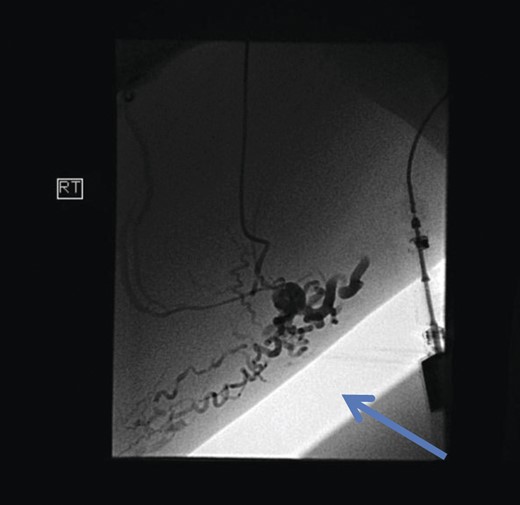

The superficial external pudendal vein was embolized with 1% sodium tetradecyl sulphate and then coiled through a contralateral puncture under fluoroscopic guidance (Figs 3 and 4). The procedure went uneventfully with successful obliteration of the communicating thigh veins to vulval varices (Fig. 5) and the patient was discharged home the same day.

Pre-embolization fluoroscopy showing communication of thigh veins to vulval varices (blue arrow).